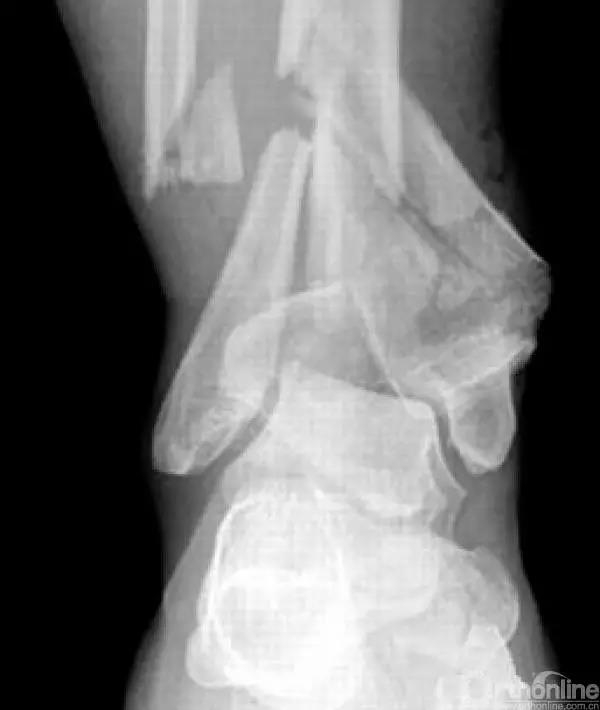

Pilon骨折为发生于胫骨远端并累及关节面,由垂直暴力合并或不合并扭转暴力导致的骨折,常表现为干骺端的压缩和关节面的粉碎。它是踝部的复杂骨折,以高能量损伤、不稳定、软组织损伤严重为特点。

临床手术复杂,并发症常见且严重。一旦治疗失败,常常带来灾难性的后果,如截肢、严重创伤性关节炎后期再关节融合等。